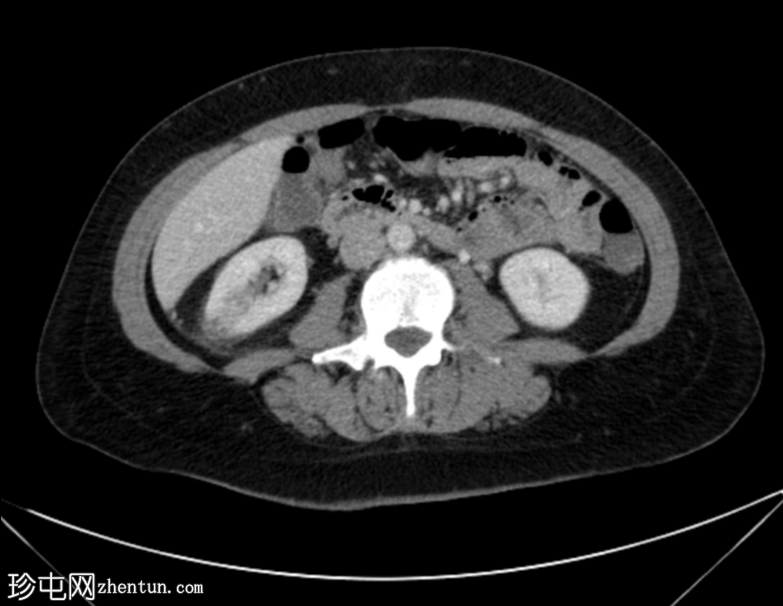

轴位增强扫描(延迟期)

右肾轴位和冠状位图像均显示肾实质下部低强化区域,伴肾周脂肪间隙模糊,符合急性肾盂肾炎的

影像

学表现。

膀胱壁轻度环周增厚及强化,可能为轻度膀胱炎。